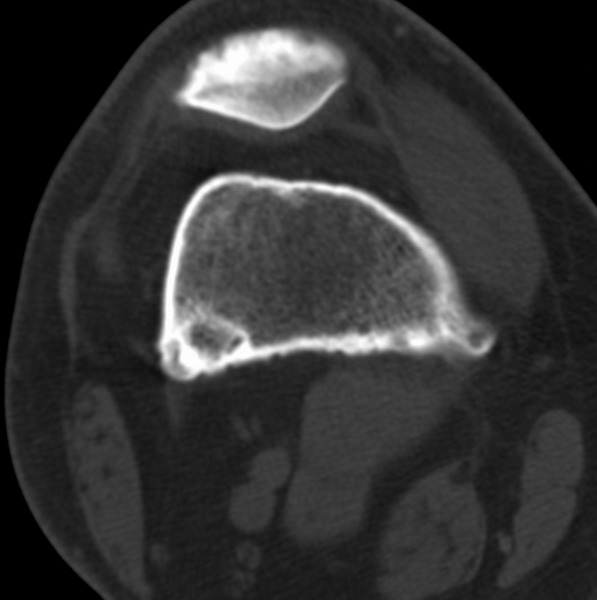

右侧膝关节疼痛一月

男、48

股骨下段、胫骨上段。

1、股骨干骺端病变考虑干骺端纤维性皮质缺损愈后(非骨化性纤维瘤)改变,胫骨近端内生骨瘤;

2、骨关节炎,骨质增生,股骨外侧髁退变性囊肿(关节面软骨下囊肿);

支持非骨化性纤维瘤

非骨化性纤维瘤